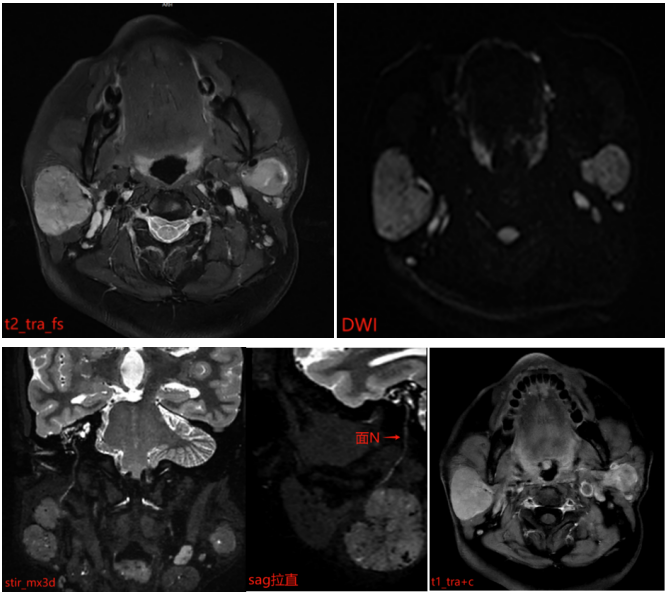

MR 表现: 双侧腮腺浅叶下极见结节状略混杂信号,T1 以低信号为主、T2 以稍高信号为主,DWI 呈稍高信号,ADC 图呈稍低信号,边界清晰,增强扫描病变中等强化,强化较均匀,其内见点状无强化影。

位置: 双侧腮腺浅叶下极(靠近下颌角)

形态: 结节状、边界清晰,内部信号略混杂

T1 低信号+T2 稍高信号: 提示内部含液体或疏松组织,常见于腮腺良性肿瘤(如多形性腺瘤)或炎性结节

DWI 高信号+ADC 低信号: 反映水分子扩散受限,需警惕细胞密集型肿瘤

增强扫描:中等均匀强化(支持肿瘤性病变),内部点状无强化区可能为小囊变或坏死灶